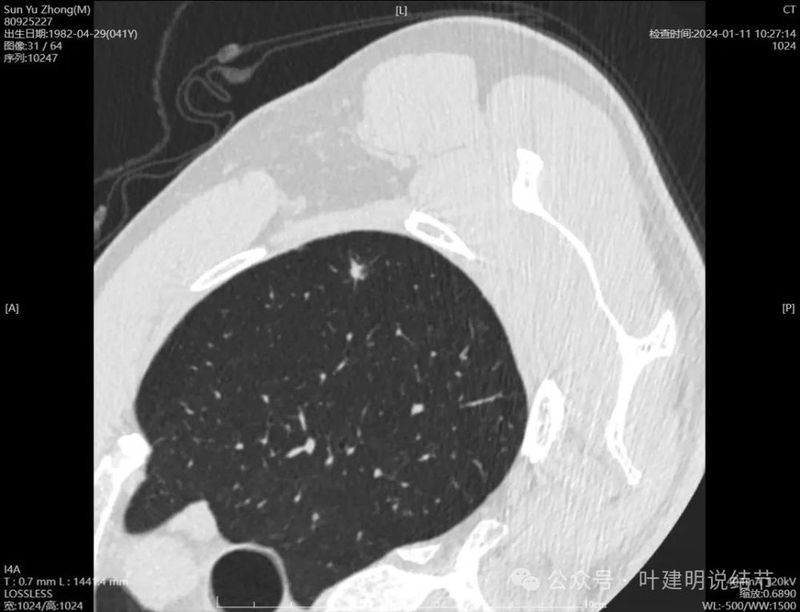

右侧病灶连续层面:

病灶出现,密度较淡。

轮廓清楚,血管贴边,也有血管弯征,瘤肺边界清楚。

轮廓与边界清,没有明显实性成分。

中间的密度稍低于周围部位。

轮廓清楚,边缘不光滑。

边缘区较淡。